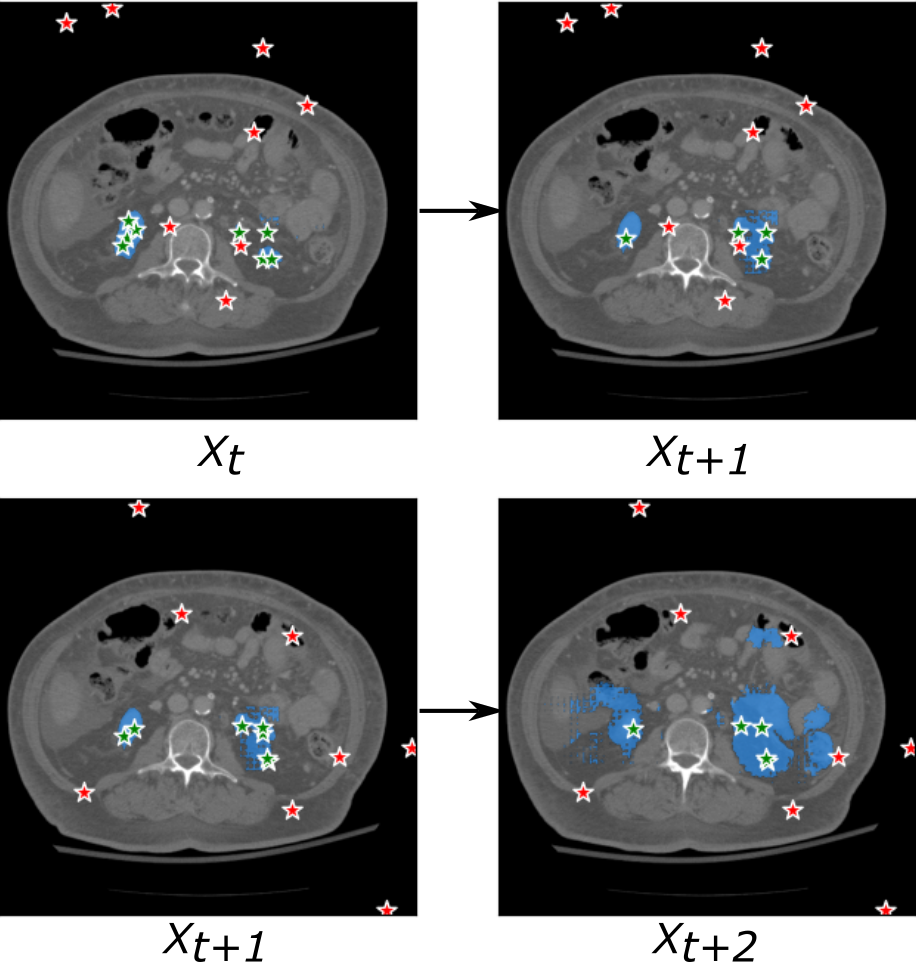

As for the ‘prompt propagation’ strategy described in Algorithm 1, the points that are randomly selected from the annotated slices will undergo propagation to the neighboring slices utilizing a straightforward thresholding rule. This iterative procedure will terminate when there are no points satisfying the specified criterion. To improve the robustness, the propagation is individually applied to each annotated slice. Consequently, in the case of two annotated slices, the propagation is executed twice, and the resulting segmentation are then ensemble to obtain the final segmentation. One example of point propagation procedure is shown in Figure 11.

Secondly, we investigated the effectiveness of the proposed SAM model in further accelerating the annotation process. In this study, we presented a straightforward ‘prompt propagation’ strategy that utilizes a simple thresholding criterion. However, the results shown in Figure 12 indicate that this strategy did not yield satisfactory performance. We identified that the success of the propagation strategy heavily relies on the selection of appropriate stop criteria. As illustrated in Figure 14, an inappropriate criterion led to severe over-segmentation in tissues with complex anatomical structure, such as kidney. The propagation strategy exhibited notably improved performance in liver segmentation task due to its simple anatomical structure.